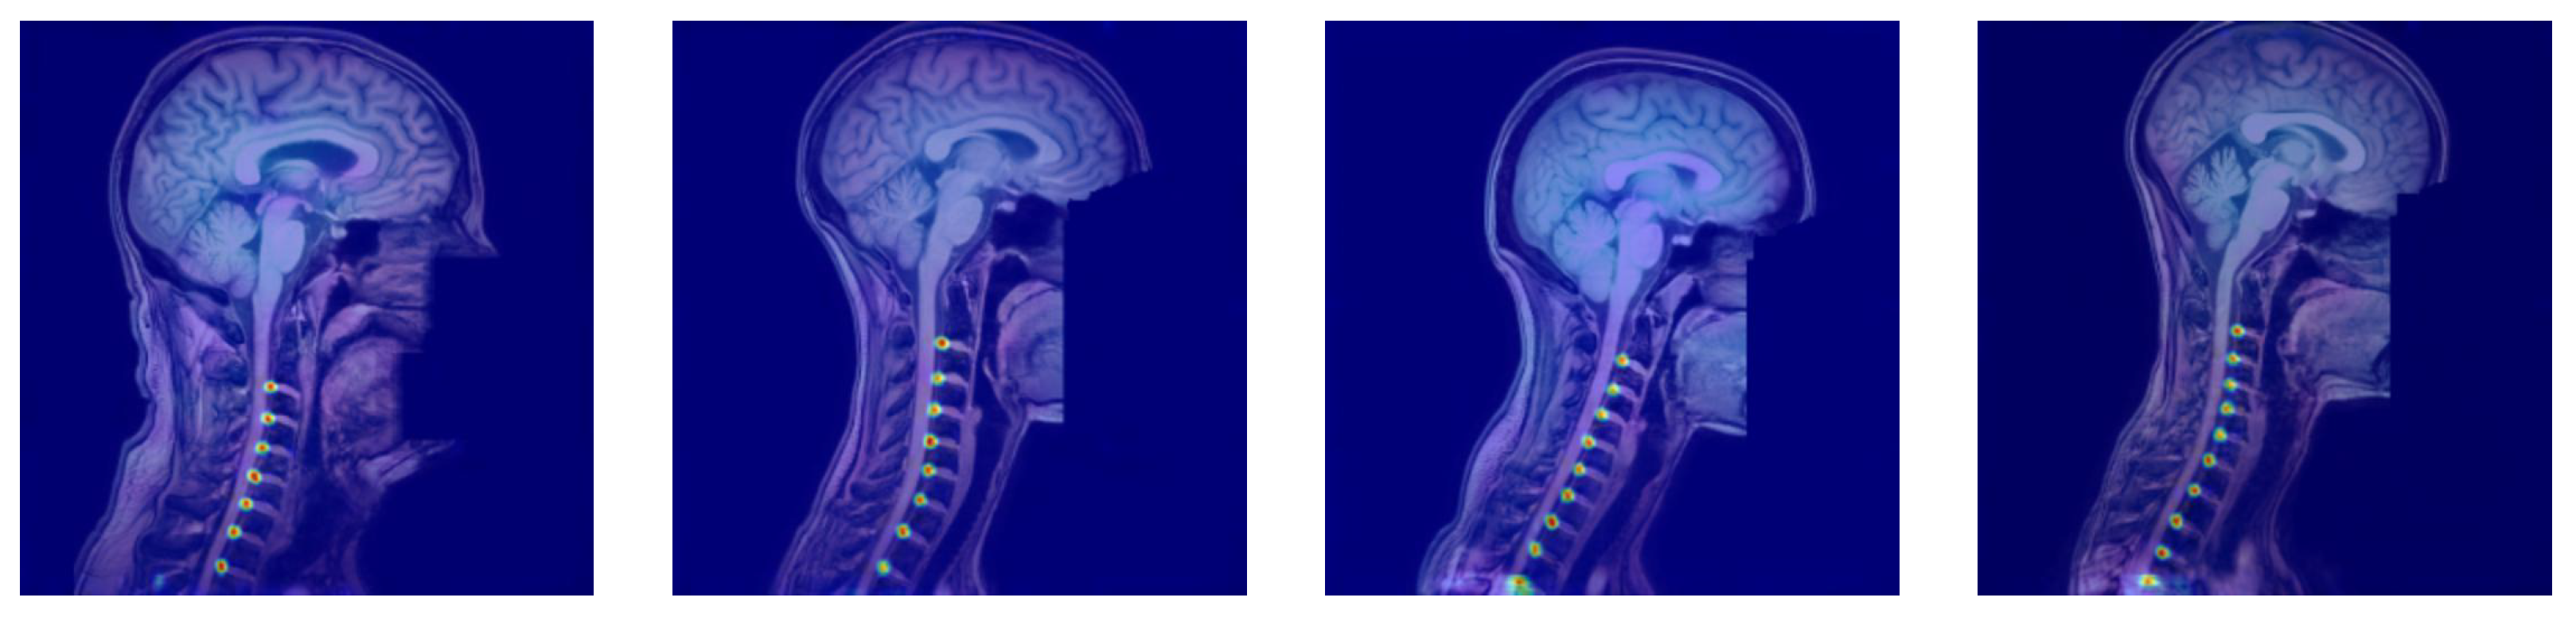

Figure 3 and Figure 4 provide representative qualitative results for MSA-Net on T1-weighted spine MRI. The predicted masks exhibit strong alignment with ground truth labels, particularly in the central disc regions. The model maintains tight localization even in images with low contrast or anatomical curvature. Notably, the method avoids common errors such as mislabeling vertebrae or merging adjacent discs, which were frequent in baseline models. In some cases involving pathological deformation or disc degeneration, minor under-segmentation occurs at disc boundaries. However, the predicted regions still provide accurate centroid locations, preserving the labeling task’s clinical value. These instances expose a limitation of the method, as it has not been explicitly trained to handle such anatomical extremes. Even in these challenging cases, our method maintains better performance than existing alternatives, demonstrating its robustness to anatomical variability.

Figure 4. The heatmap outcomes of the proposed approach for identifying intervertebral disc positions in MRI T1 scans. The method generates spatial probability maps that highlight disc regions and reinforce localization confidence across the spinal column.